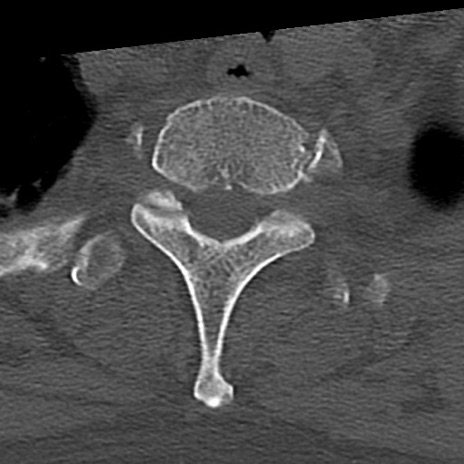

頚椎CT

横断像